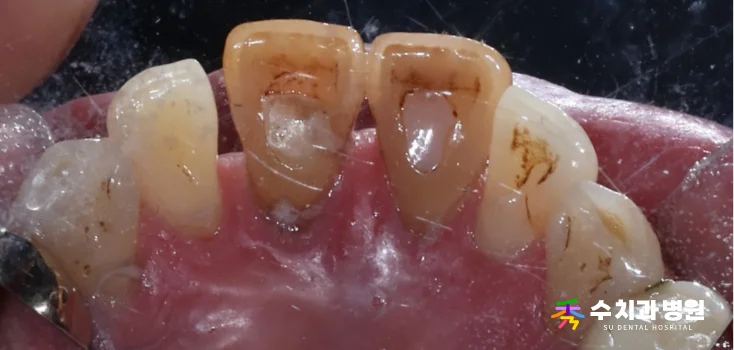

🔍 치료 전 (Before)

[치료 전 사진] (촬영일: 2025년 06월)

환자분은 앞니 하나가

점점 아래로 처지는 느낌이 들어

걱정스러운 마음에 내원하셨습니다.

정밀 검사 결과, 오른쪽 대문니(앞니)는

과거에 신경치료를 받았던 이력이 있었습니다.

뿌리 쪽 잇몸뼈 흡수가 심하게 진행되어

치아가 제 위치를 잡지 못하고 있었습니다.

치아가 심하게 흔들리는 상태였기 때문에

안타깝게도 발치가 불가피했습니다.

또한 옆 치아의 색상도 변색이 진행되어

심미적인 개선이 시급했습니다.